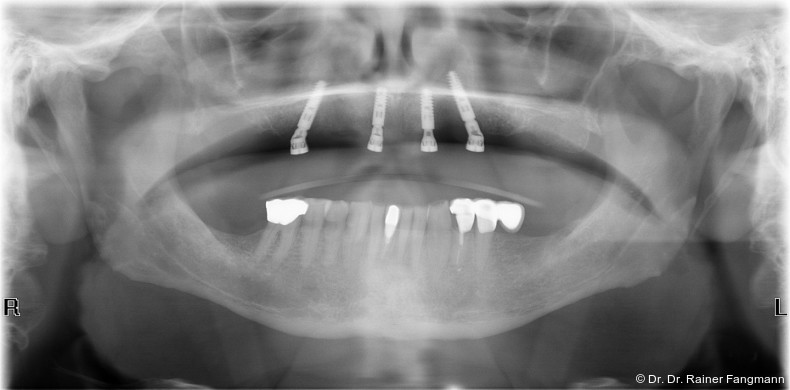

Der atrophierte Unterkiefer bietet in der Regel ein nicht ausreichendes Lager. Die totalprothetische Versorgung des zahnlosen Oberkiefers bedingt stets eine gaumenbedeckende Konstruktion. „Der Platz, der dem implantologischen Chirurgen für die Positionierung der Zahnimplantate zur Verfügung steht, kann durch anatomische Gegebenheiten wie einen stark pneumatisierten Sinus maxillaris oder einen eher koronalen Verlauf des Canalis mandibularis eingeschränkt werden.“ Zudem kann das in vertikaler und horizontaler Ebene reduzierte krestale Knochenvolumen mit und ohne schlechte Knochenqualität den Therapieansatz noch weiter verkomplizieren. So ist seit 2000 das Konzept der schräginserierten Implantate entstanden und verfolgt worden.3 Eine von Zampelis et al. durchgeführte In-vitro-Studie hat bewiesen, dass eine schräge Insertion von prothetischen verblockten Implantaten nicht zu einer größeren Belastung führt als bei parallel gesetzten Implantaten.3 Die Digitalisierung der Zahnmedizin und -technik und der zunehmende Wunsch der Patienten nach festsitzenden Versorgungen führten zudem zu einer vermehrten Verbreitung dieses nach seinem Erstbeschreiber Maló benannten Konzeptes. Ebenso haben immer mehr Implantatanbieter die spezifischen abgewinkelten Aufbauelemente in ihr Portfolio aufgenommen. „In prothetischer Hinsicht ist es letztlich auf einer geringeren Anzahl von Implantaten einfacher, eine spannungsfreie Passung der Stege zu erreichen.“

Die Fragestellung nach der angemessenen Implantatanzahl für implantatgetragenen Zahnersatz bei zahnlosen Kiefern wird immer wieder aufgeworfen. Das All-on-X-Konzept sieht eine festsitzende bzw. bedingt festsitzende Versorgung im zahnlosen Kiefer vor. Naujakat, Behrends und Wiltfang kommen 2018 zu folgender Feststellung: Beim zahnlosen Oberkiefer eignen sich in der Regel mindestens sechs Implantate und im Unterkiefer mindestens vier Implantate festsitzend.4 Wolfart und Kern vertraten 2016 die Ansicht, wünscht der Patient einen festen Halt seines Zahnersatzes oder liegt ein sehr ausgeprägter Knochenabbau in vertikaler Dimension vor, wird eine Versorgung aufStegen (vier bis sechs Implantate) oder Teleskopen (sechs Implantate) gewählt.5 Im Oberkiefer heißt es: „Wünscht der Patient eine starre Lagerung der Prothese, um wieder das Gefühl von festen Zähnen zu haben, sind vier bis sechs Implantate notwendig. Diese werden entweder mit Teleskopen (sechs Implantate) oder mit einem parallel gefrästen Steg (vier bis sechs Implantate) versorgt. […] Wünscht der Patient explizit eine festsitzende Restauration, so ist hierfür die Insertion von mindestens fünf Implantaten notwendig.“6 Retrospektiv berichten Maló et al. (2019) in ihrer Studie über das „All-on-4“-Konzept mit Sofortbelastung zur Rehabilitation des zahnlosen Oberkiefers bei insgesamt 1.072 Patienten mit einer Nachbeobachtung von fünf bis 13 Jahren über eine Überlebens- und Erfolgsrate der Implantate von 93,9 Prozent bei einer Nachbeobachtung von bis zu 13 Jahren. Die Schlussfolgerung für das All-on-4-Behandlungskonzept im Hinblick auf das Langzeitergebnis gilt als vorhersehbar und sicher.7 Zu diesem Schluss kam Heydecke in seiner Übersichtsarbeit bereits 2012.8

Ein immer viel diskutiertes Thema ist die Implantatanzahl beim All-on-X-Konzept. Diese ist von vielen Faktoren abhängig. Zu nennen sind der Implantattyp, der Implantatdurchmesser und die Implantatinnengeometrie. Im Weiteren sind die Knochenqualität und -quantität zu betrachten. Auch spielt die Gegenbezahnung zum All-on-X-Kiefer eine entscheidende Rolle, sodass hier keine einheitliche Linie für den Oberkiefer erkennbar ist. Es gelten in der Regel vier bis sechs Implantate als ausreichend. Im Unterkiefer sind es in der Regel vier. Wie dargestellt, reichen bei diesem Implantatsystem auch drei Implantate aus.